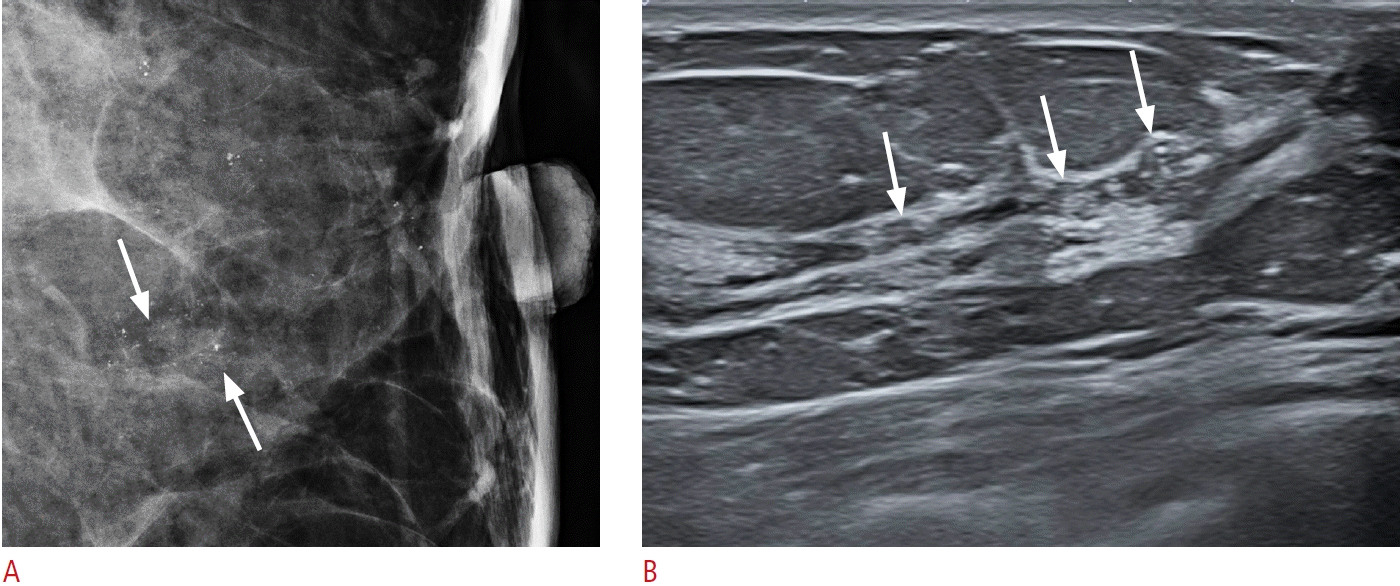

21. Lee SJ, Sobel LD, Shamis M, Mahoney MC. Asymmetric ductal ectasia: an often overlooked sign of malignancy. AJR Am J Roentgenol. 2019; 213:473–481.

17. Ban K, Tsunoda H, Watanabe T, Kaoku S, Yamaguchi T, Ueno E, et al. Characteristics of ultrasonographic images of ductal carcinoma in situ with abnormalities of the ducts. J Med Ultrason (2001). 2020; 147:107–115.

18. Watanabe T, Yamaguchi T, Tsunoda H, Kaoku S, Tohno E, Yasuda H, et al. Ultrasound image classification of ductal carcinoma in situ (DCIS) of the breast: analysis of 705 DCIS lesions. Ultrasound Med Biol. 2017; 43:918–925.